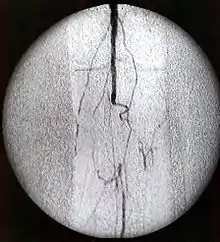

Contrastes radiológicos yodados

Se trata del grupo más importante dentro de los medios de contraste, ya que son los más usados. Se caracterizan por una alta densidad de contraste y una baja toxicidad.

Los contrastes yodados se pueden administrar tanto por vía oral, como por vía endovenosa, y dependiendo de la vía de administración, presentaran características farmacocinéticas diferentes.

Los contrastes yodados administrados por vía oral se absorben muy poco y se eliminan fácilmente por vía rectal, mientras que los administrados por vía endovenosa, se eliminan prácticamente de forma total por vía renal, y es solo un 2% excretado por vía biliar.